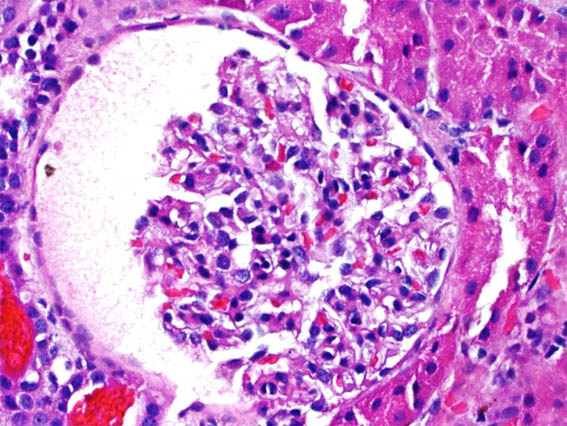

Figura 4. H&E, X400.